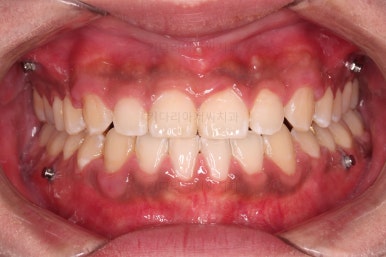

가지런한 느낌, 앞니 뻐드러짐을 좋게 했고요.

교합도 맞춰 위아래가 톱니바퀴처럼 맞물리게 했고, 앞니도 위아래 관계를 잘 맞추고 마무리를 했습니다.

전후 비교해 볼게요.

1년 3개월이라는 비교적 짧은 기간안에 적절한 교합, 심미성 등 여러 가지를 달성했던 만족스러운 치료였습니다.